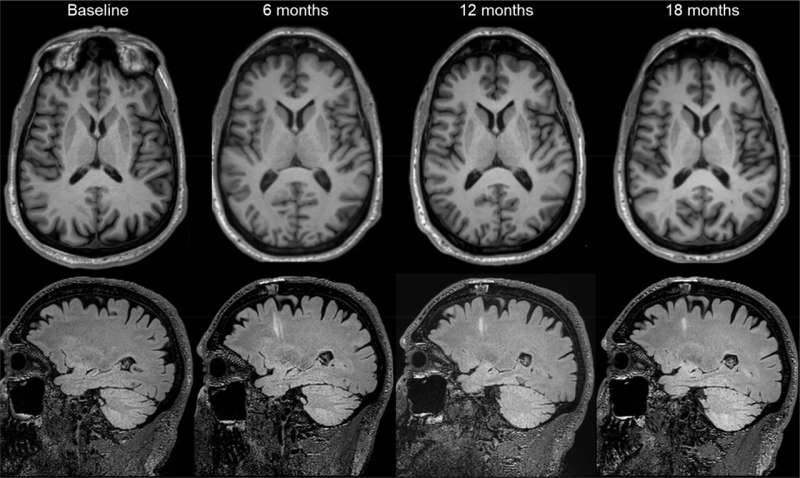

第二項試驗在美國和加拿大各地進行,Viviane Tabar及其同事探究了源自人類胚胎干細胞的多巴胺能神經(jīng)元祖細胞產(chǎn)品(bemdaneprocel)的安全性。12名患者(平均年齡67歲)接受了手術(shù),將bemdaneprocel移植到大腦兩側(cè)的殼核。5名參與者接受了低劑量(每核0.9百萬個細胞),7名參與者接受了高劑量(每核2.7百萬個細胞)。

與日本的研究類似,沒有出現(xiàn)與引入細胞相關的死亡、嚴重不良事件或腫瘤樣組織生長。試驗參與者總共報告了兩起嚴重事件。一名參與者因感染新冠肺炎住院,另一名參與者因手術(shù)而癲癇發(fā)作。

該細胞產(chǎn)品總體耐受性良好,在18個月的隨訪期內(nèi)未報告與治療相關的嚴重不良事件。此外,未出現(xiàn)此前用于治療帕金森病的胎兒組織移植相關運動障礙的發(fā)生。

此外,低劑量組和高劑量組患者的運動功能均有所改善(這是該研究的次要結(jié)果)。然而,不同測量參數(shù)的改善程度存在差異。